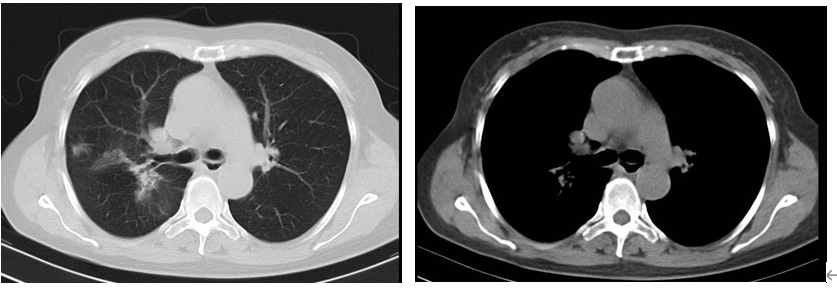

治疗前基线:右肺上叶多发结节,大者(2.3*2.0*2.1cm)考虑恶性。

治疗2月后:(SD)右肺上叶多发结节,大者(2.0*1.5*1.8cm)恶性可能性大。

治疗8月后:(PR)右肺上叶多发结节,大者(1.2*1.1cm)较前明显缩小。

治疗13个月后(2021-8):(PR)

本2例患者均为右肺腺癌,EGFR 21 L858R+EGFR 20 T790M,伴淋巴结转移、骨转移,Ⅳ期。

初始治疗均选用阿美替尼110mg qd,目前均为PR,CASE1 PFS>22个月,CASE2 PFS>18个月,疗效显著。